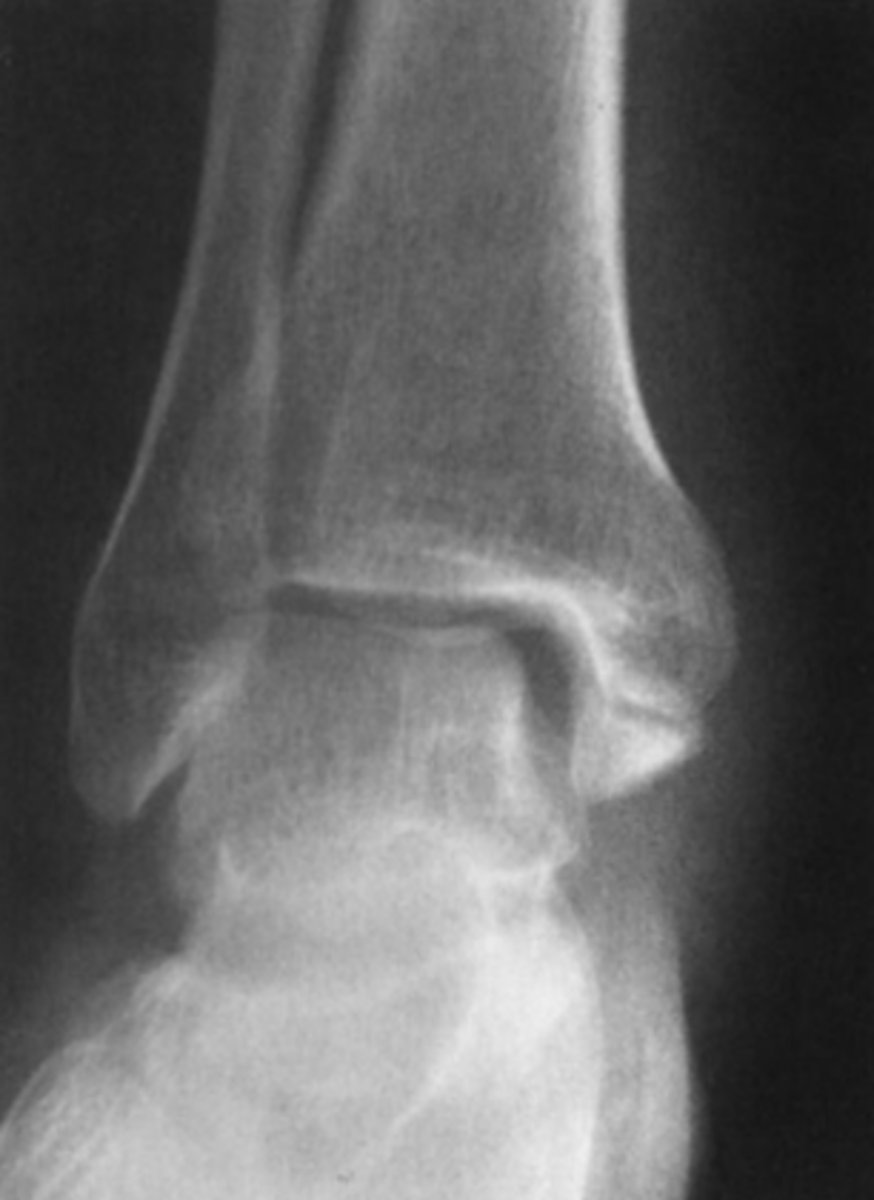

A week later you are once again moonlighting in the same small emergency department when a 29-year-old man is carried in complaining of ankle pain after a twisting injury. His ankle is swollen and ecchymotic, and he is tender to palpation along the medial malleolus. He has no other complaints.

You order frontal, lateral, and oblique views of the ankle (AP view of the ankle).

You examine the radiographs for Case 6-4. Only the

AP view is shown here (Figure 6-11). You tell the pa-

tient he has broken his ankle, but you want to get one

more study:

A. Entire tibia and fibula, to exclude more proximal

fractures

B. Ipsilateral foot, to exclude a fracture of the fifth

metatarsal

C. Contralateral ankle, for comparison purposes

D. CT, for precise evaluation of the alignment of the

fracture

Answer

A.

Transverse fracture of the distal medial malleolus with widening of the medial aspect of the ankle joint. We see this with a proximal fibular fracture or maissoneuve. You should get these views to rule out involvement of the proximal fibula and syndesmosis injury.